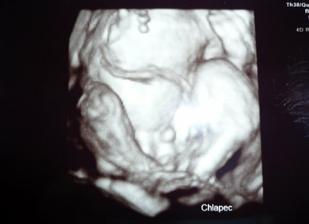

8.2. o 2:55hod sa nam narodil náš chrústik Tomáško, meral 51cm a vážil 3680g,po príchode z pôrodnice vážil 3430g a na poradni v 5 týždnoch meral 59,5cm a vážil 4810g.

Náš vytúžený chrústik Tomáško